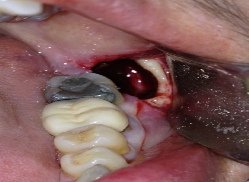

ΑΚΡΟΡΡΙΖΕΚΤΟΜΗ ΚΑΙ ΑΝΑΣΤΡΟΦΗ ΕΜΦΡΑΞΗ ΣΕ ΑΠΟΝΕΥΡΩΜΕΝA  ΔΟΝΤΙA ΚΑΙ ΑΦΑΙΡΕΣΗ ΚΥΣΤΕΩΝ